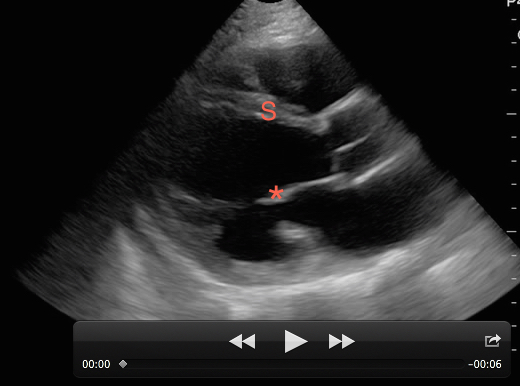

While viewing the cardiac windows gain a sense of the overall cardiac function and ejection fraction (EF). Emergency sonographers can categorize cardiac contractility as normal, depressed, or severely depressed and identify a severely depressed left ventricular EF with nearly 100% sensitivity.[9] The anterior leaflet of the mitral valve will touch or nearly touch the inter-ventricular septum in a heart with a normal EF. You may choose to measure the distance from the anterior leaflet of the mitral valve during diastole from the inter-ventricular septum with M-Mode. A distance of less than 7 mm suggests a normal EF whereas greater than 7 mm is 100% sensitive for a severely depressed EF. This is known as E-Point Septal Separation or EPSS. [10] In the apical four-chamber view, compare the right ventricle (RV) to left ventricle (LV) diameter. A normal RV is less than 2/3 the size of the LV. A dilated RV in the right setting is 98% specific of right heart strain from a pulmonary embolism. [11] You also may note a wall motion abnormality as evidence of old or new myocardial infarction. If color is added to the exam valve incompetence can be identified.

Figure 4. A poorly contracting heart in the setting of decompensated heart failure. The anterior leaflet of the mitral valve (*) does not come close to the inter-ventricular septum (S) during diastole demonstrating a severely depressed EF.